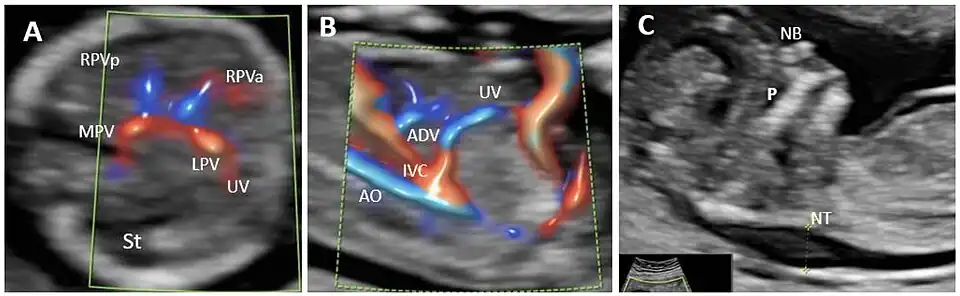

In the fetus, the ductus venosus ("DV"; Arantius' duct after Julius Caesar Aranzi[1]) shunts a portion of umbilical vein blood flow directly to the inferior vena cava.[2] Thus, it allows oxygenated blood from the placenta to bypass the liver. Compared to the 50% shunting of umbilical blood through the ductus venosus found in animal experiments, the degree of shunting in the human fetus under physiological conditions is considerably less, 30% at 20 weeks, which decreases to 18% at 32 weeks, suggesting a higher priority of the fetal liver than previously realized.[3] In conjunction with the other fetal shunts, the foramen ovale and ductus arteriosus, it plays a critical role in preferentially shunting oxygenated blood to the fetal brain. It is a part of fetal circulation.

The pathway of fetal umbilical venous flow is

umbilical vein left portal vein ductus venosus inferior vena cava eventually right atrium.